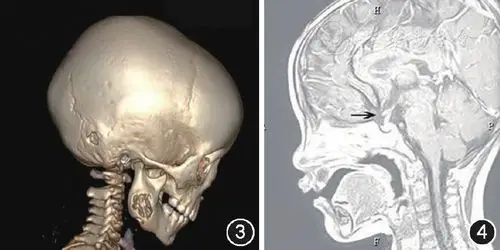

利用3d软件对患者术前颅底ct数据进行三维重建,打印3d头颅颅骨模型

标志红色点为卵圆孔处利用3d软件对患者术前颅底ct数据进行三维重建

图3朗格罕组织细胞增生症患儿头颅ct三维重建示右侧下颌骨及颞骨近